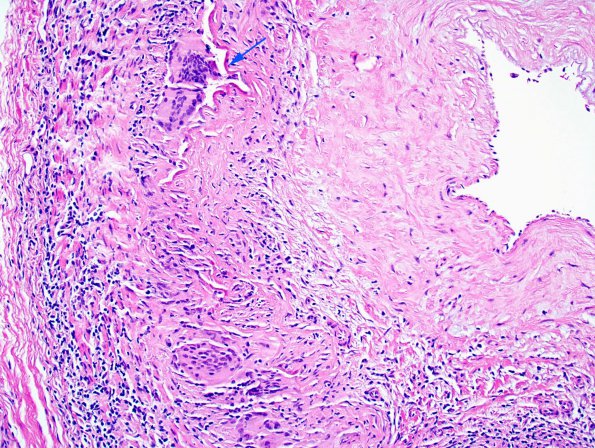

Vasculitis - Giant Cell Arteritis

7A2 Temporal Arteritis (Case 7) 4 copy

Higher magnification of image #7A2. (H&E)